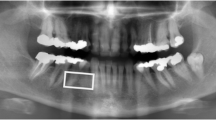

The selection of the ROIs was done according to anatomical landmarks in order to be reproducible. The femoral neck ROI was chosen by positioning the two points in the middle of the upper and the lower borders of the femoral neck so that the ROI lies in the middle of the femoral neck approximately at the anatomical Ward’s triangle (Fig. 1a). For the greater trochanter ROI, one point was positioned at the junction of the greater trochanter and the femoral neck, and the other, at the edge of the greater trochanter on a line perpendicular to the axis of the femur (Fig. 1b). For the intertrochanteric ROI, one point was positioned at the junction of the greater trochanter and the femoral neck, and the other, at the upper edge of the lesser trochanter (Fig. 1c). The texture parameters given by the device for each ROI are the fractal dimension (Hmean), the co-occurrence matrix, and the run length matrix.